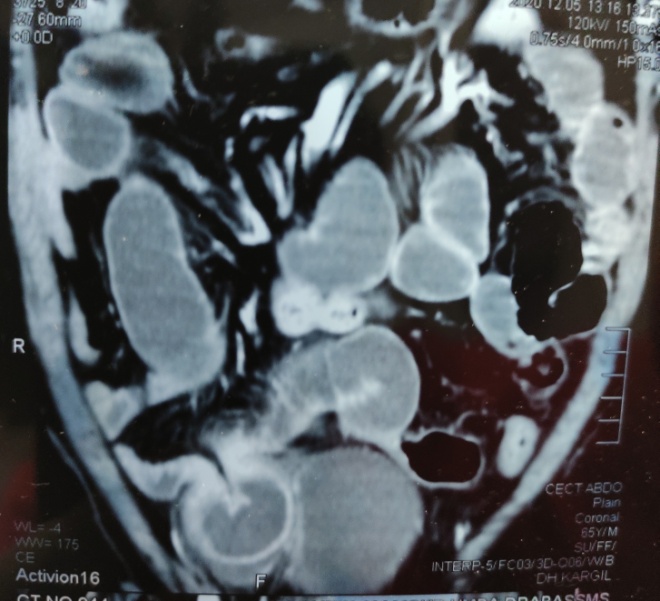

An elderly man presented with a history of colicky abdominal pain and vomiting of 5 days duration. He had a history of exploratory laparotomy for duodenal perforation peritonitis some 20-30 years back. He was having left hemi-paresis due to a stroke 2 years back. He also had history of left uncomplicated inguinal hernia for the last 3 years. On examination, he was dehydrated with a heart rate of 100bpm, blood pressure of 120/86mmHg, and a temperature of 370C. His abdomen was distended, mildly tender and having a previous long midline incision scar. There was also a small, direct, reducible, uncomplicated, left inguinal hernia. Blood tests showed leucocytosis. Plain film radiography showed distended small-bowel loops with air-fluid levels consistent with a small-bowel obstruction. Adhesional small-bowel obstruction was suspected clinically. C.T scan abdomen showed dilated small bowel loops. The coronal C.T image (figure 1) demonstrated a U – shaped bowel loop with a sac – like appearance, on the right side of lower abdomen just over the urinary bladder and pressing it. The axial C.T image (figure 2) showed two transition points of the pseudo-encapsulated small bowel loop above the urinary bladder. The patient underwent exploratory laparotomy and intra-operatively small-bowel obstruction due to right internal Supravesical hernia (Figure 3), was found. The closed loop obstruction had caused strangulation (Figure 4) and hence resection anastomosis of involved ileal loop was done due to doubtful viability. The hernia defect (Figure 5) was closed with interrupted 1/0 Prolene stitches. The patient recovered uneventfully and was discharged on 8th postoperative day.

Figure 1. Coronal CT showing a U-shaped bowel loop with a sac-like appearance, pressing the urinary bladder.